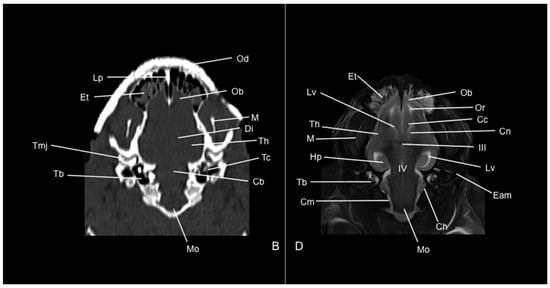

3. Results

3.1. Anatomical Study

3.2. Computed Tomography Study

3.3. Magnetic Resonance Imaging (MRI)